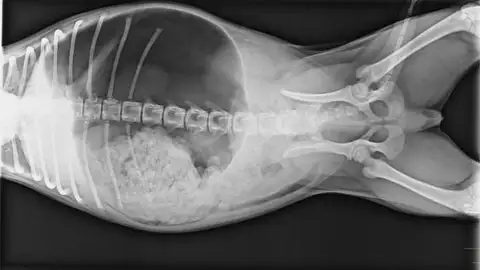

Estomago dilatado en perro

Afecta a razas de gran tamaño y la solución suele ser quirúrgica